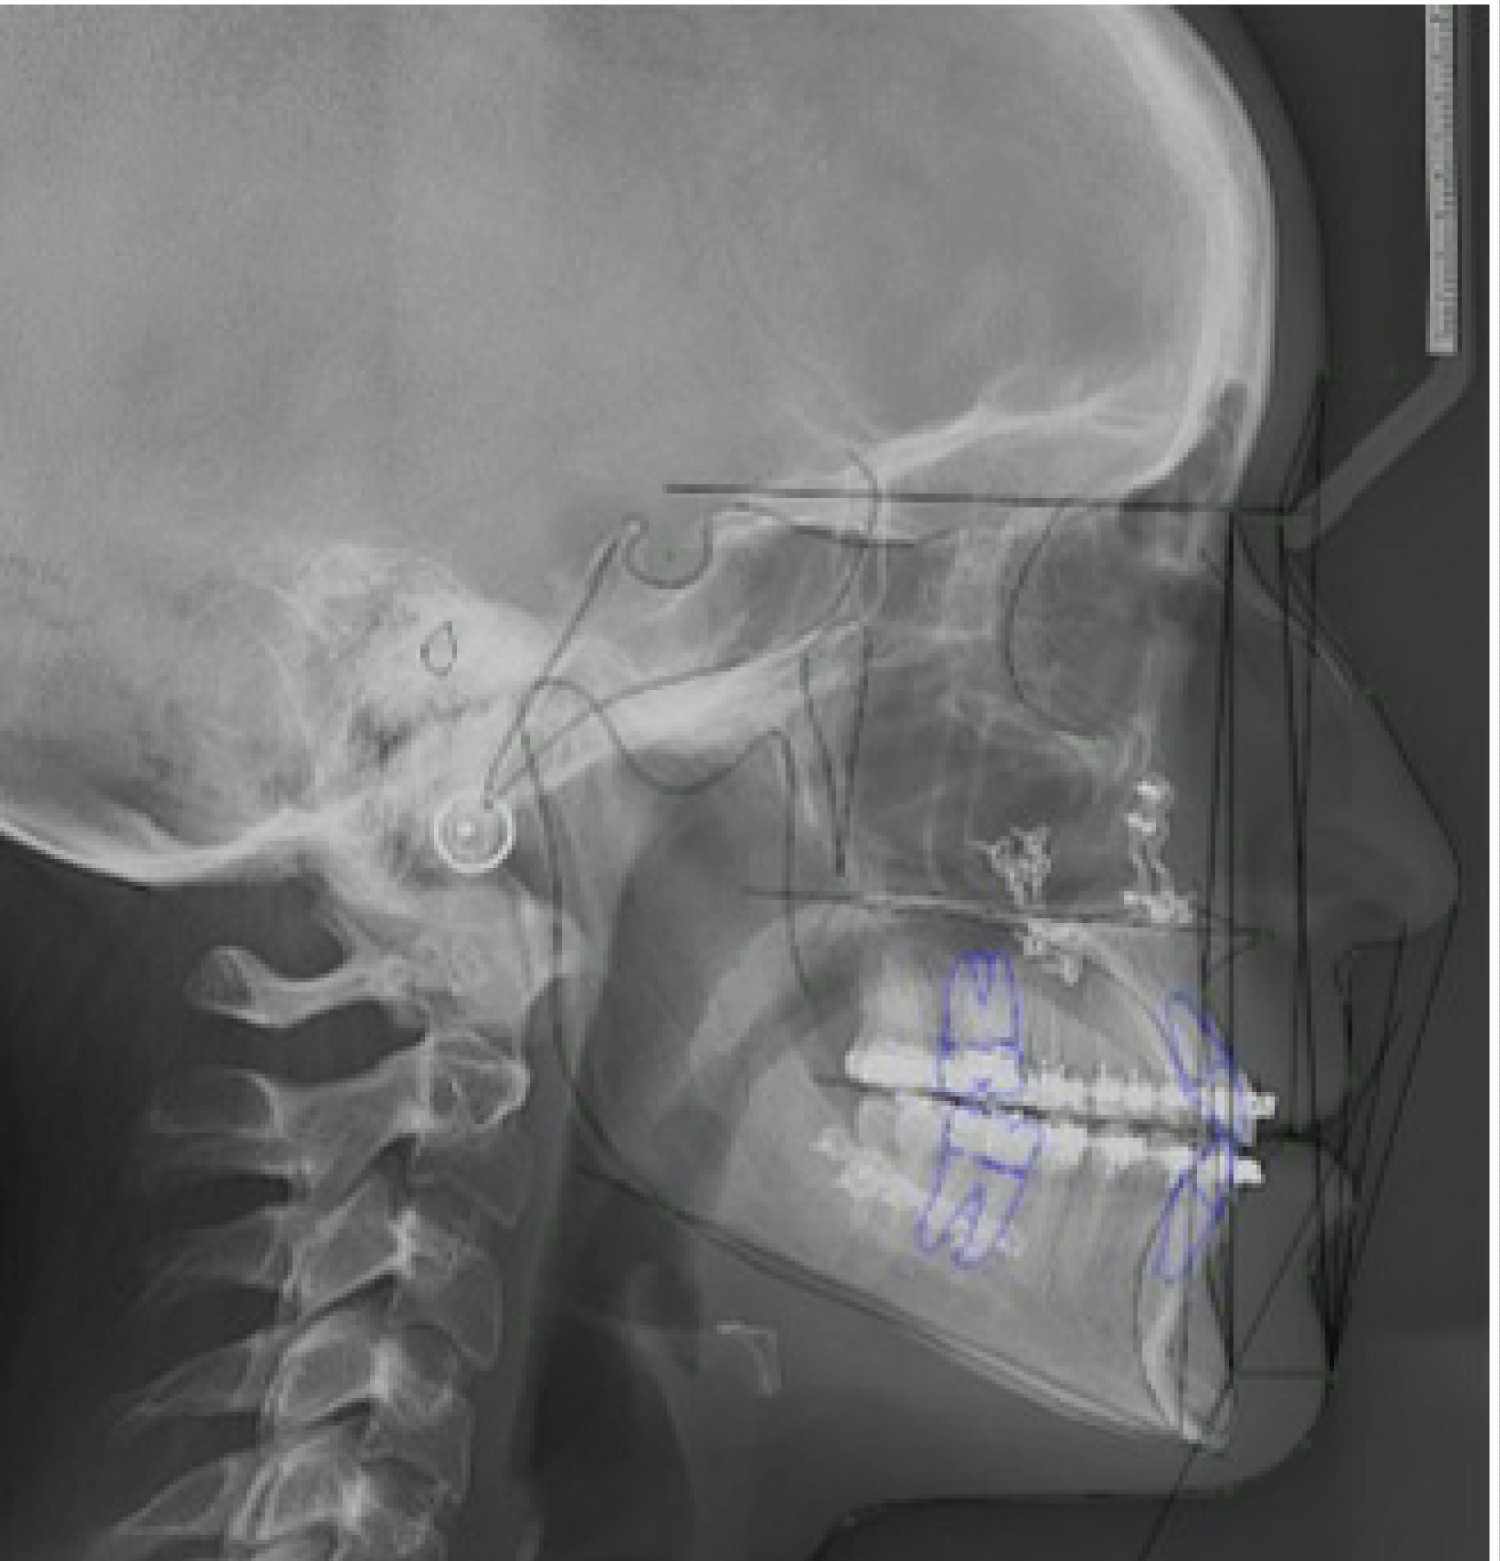

The first case was a male patient with a skeletal class III associated with a true Macrogenie. This patient was a candidate for Orthognathic Surgery with LeFort I osteotomy to decant the Maxilla, a 6 mm advance on both sides and a 2 mm descent, a bilateral sagittal osteotomy of the Mandibular Branch with a centering 3.2 mm to the left and a 0.5 mm setback, a filing at the level of the back of the septum and a 4 mm retraction and ascent Coronal Genioplasty (Figure 1, Figure 2, Figure 3, Figure 4 and Figure 5).

Figure 1: Initial patient 1: Lateral view. View Figure 1

In the case of the patients presented, the changes are exposed to the naked eye and aesthetics, but they are also expressed according to facial analyzes, for example, in the patient 1, following the reference of the Burstone and Legan Analysis [12], the distance to level of hard tissues from the Nasion point to the Pogonion, which indicates the prominence of chin in relation to profile went from being 35.3 mm to 21.5 mm and in patient 2 a, even a decrease in mandibular length measured from the Gonion to the Pogonion from 81.5 to 76.8 mm (Figure 6, Figure 7, Figure 8, Figure 9 and Figure 10).